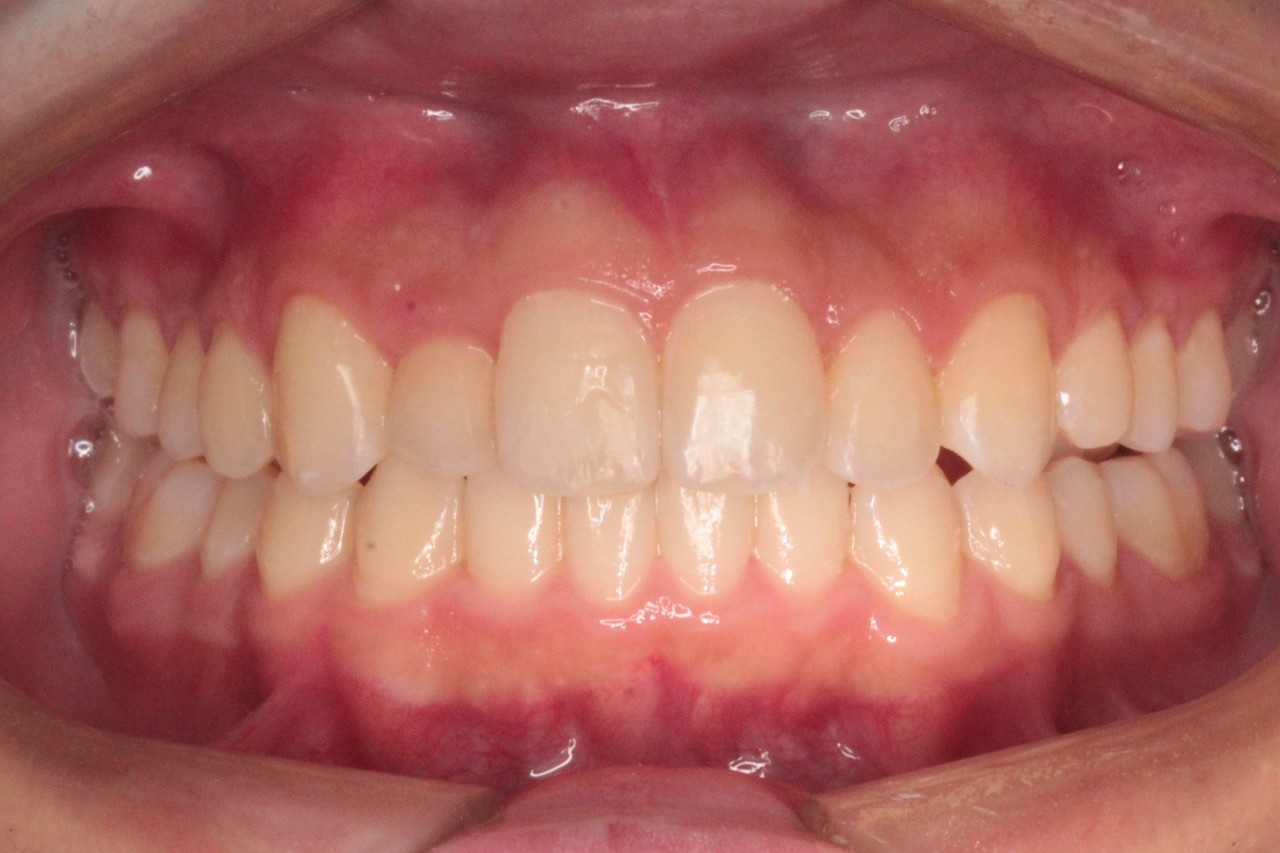

治療後

治療結果:交叉咬合と叢生が改善されました

交叉咬合と重度叢生を非抜歯のインビザラインで治療しました